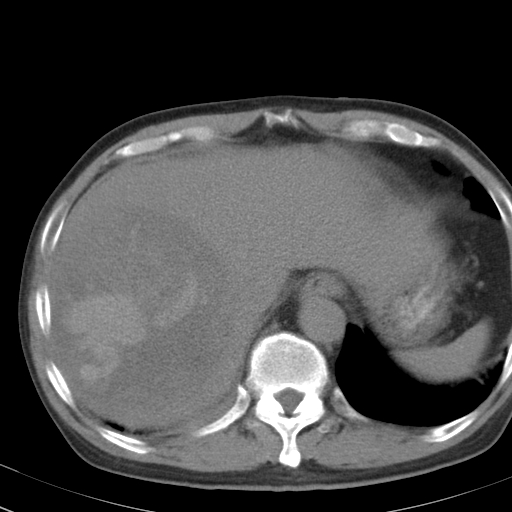

以下是引用卜一在2008-6-23 15:38:00的发言:[br]本例延时期的图象未扫完,单纯平扫 动脉期及门脉期特征分析:平扫低密度较大肿块,内见不规则出血灶,界限清楚。动脉期边缘结节样强化,门脉期病灶边缘进一步强化并范围明显缩小。因此考虑:血管瘤伴出血!

以下是引用深泽交通医院在2008-6-23 16:40:00的发言:[br]考虑肝癌伴出血.诊断依据:平扫瘤壁结节密度低于肝实质,动脉期壁结节明显强化,门脉期略低于肝实质密度[br]病灶有明显的假包膜,